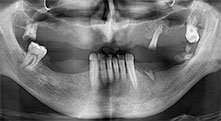

Restbezahnung

Ein 40-jähriger Patient mit desolater Restbezahnung wünscht eine Implantatversorgung. Da er Raucher ist, wird im Oberkiefer kein Sinuslift mit festem Zahnersatz, sondern eine Stegprothese auf vier anterioren Implantaten geplant.

Implantate

Die vier Implantate befinden sich wie geplant in situ. Die distalen Oberkiefermolaren dienen noch zur Fixierung der unterfütterten Prothese, die einen Monat nach Implantation eingegliedert wird.